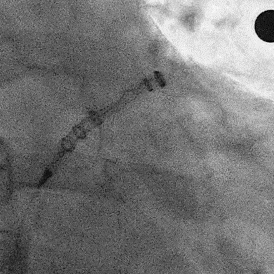

术中DSA左心耳造影+测量确认心耳形态和位置

右肩位左心耳造影

肝位左心耳造影

DSA左心耳造影

(正足位造影)

肝位左心耳测量,开口26mm,上叶深度32mm